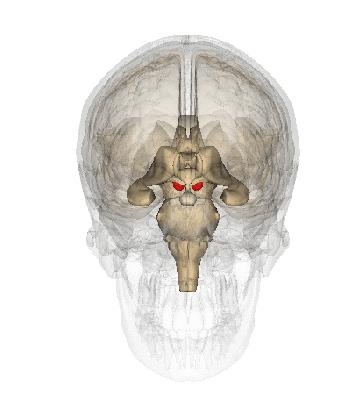

2. 脑室系统

点击图片可查看大图详情